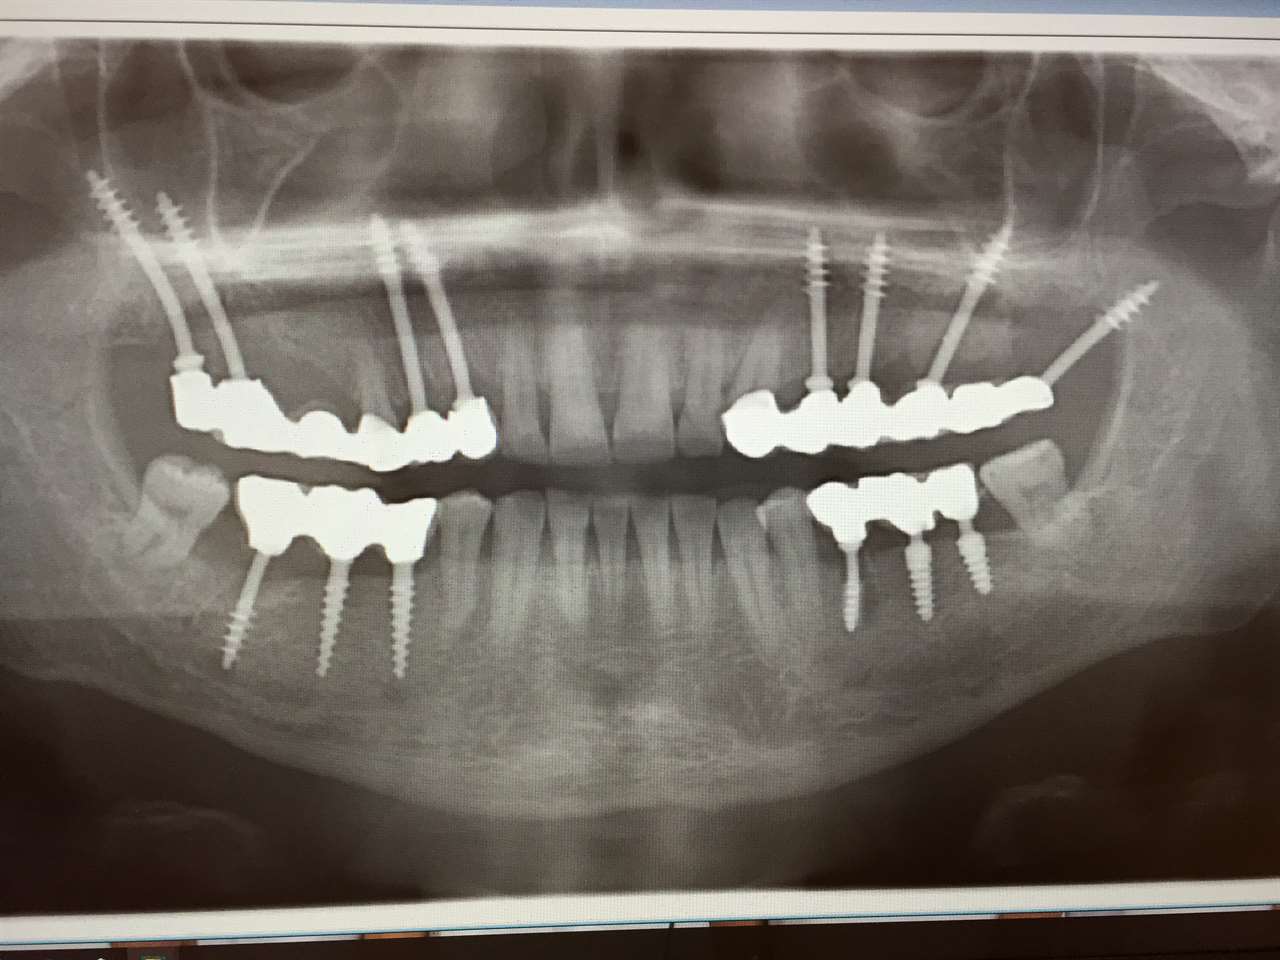

Teljes szájüregi rehabilitáció két lépésben

Ismét egy teljes szájüregi rehabilitáció két lépésben. Először az alsó fogak lettek kihúzva és azonnal implantálva, híddal ellátva, majd később a felső. IHDE svájci azonnal terhelhető implantátumok és cirkónium hidak. Dr. Kelemen Péter és a Symbion Fogtechnika közös munkája.